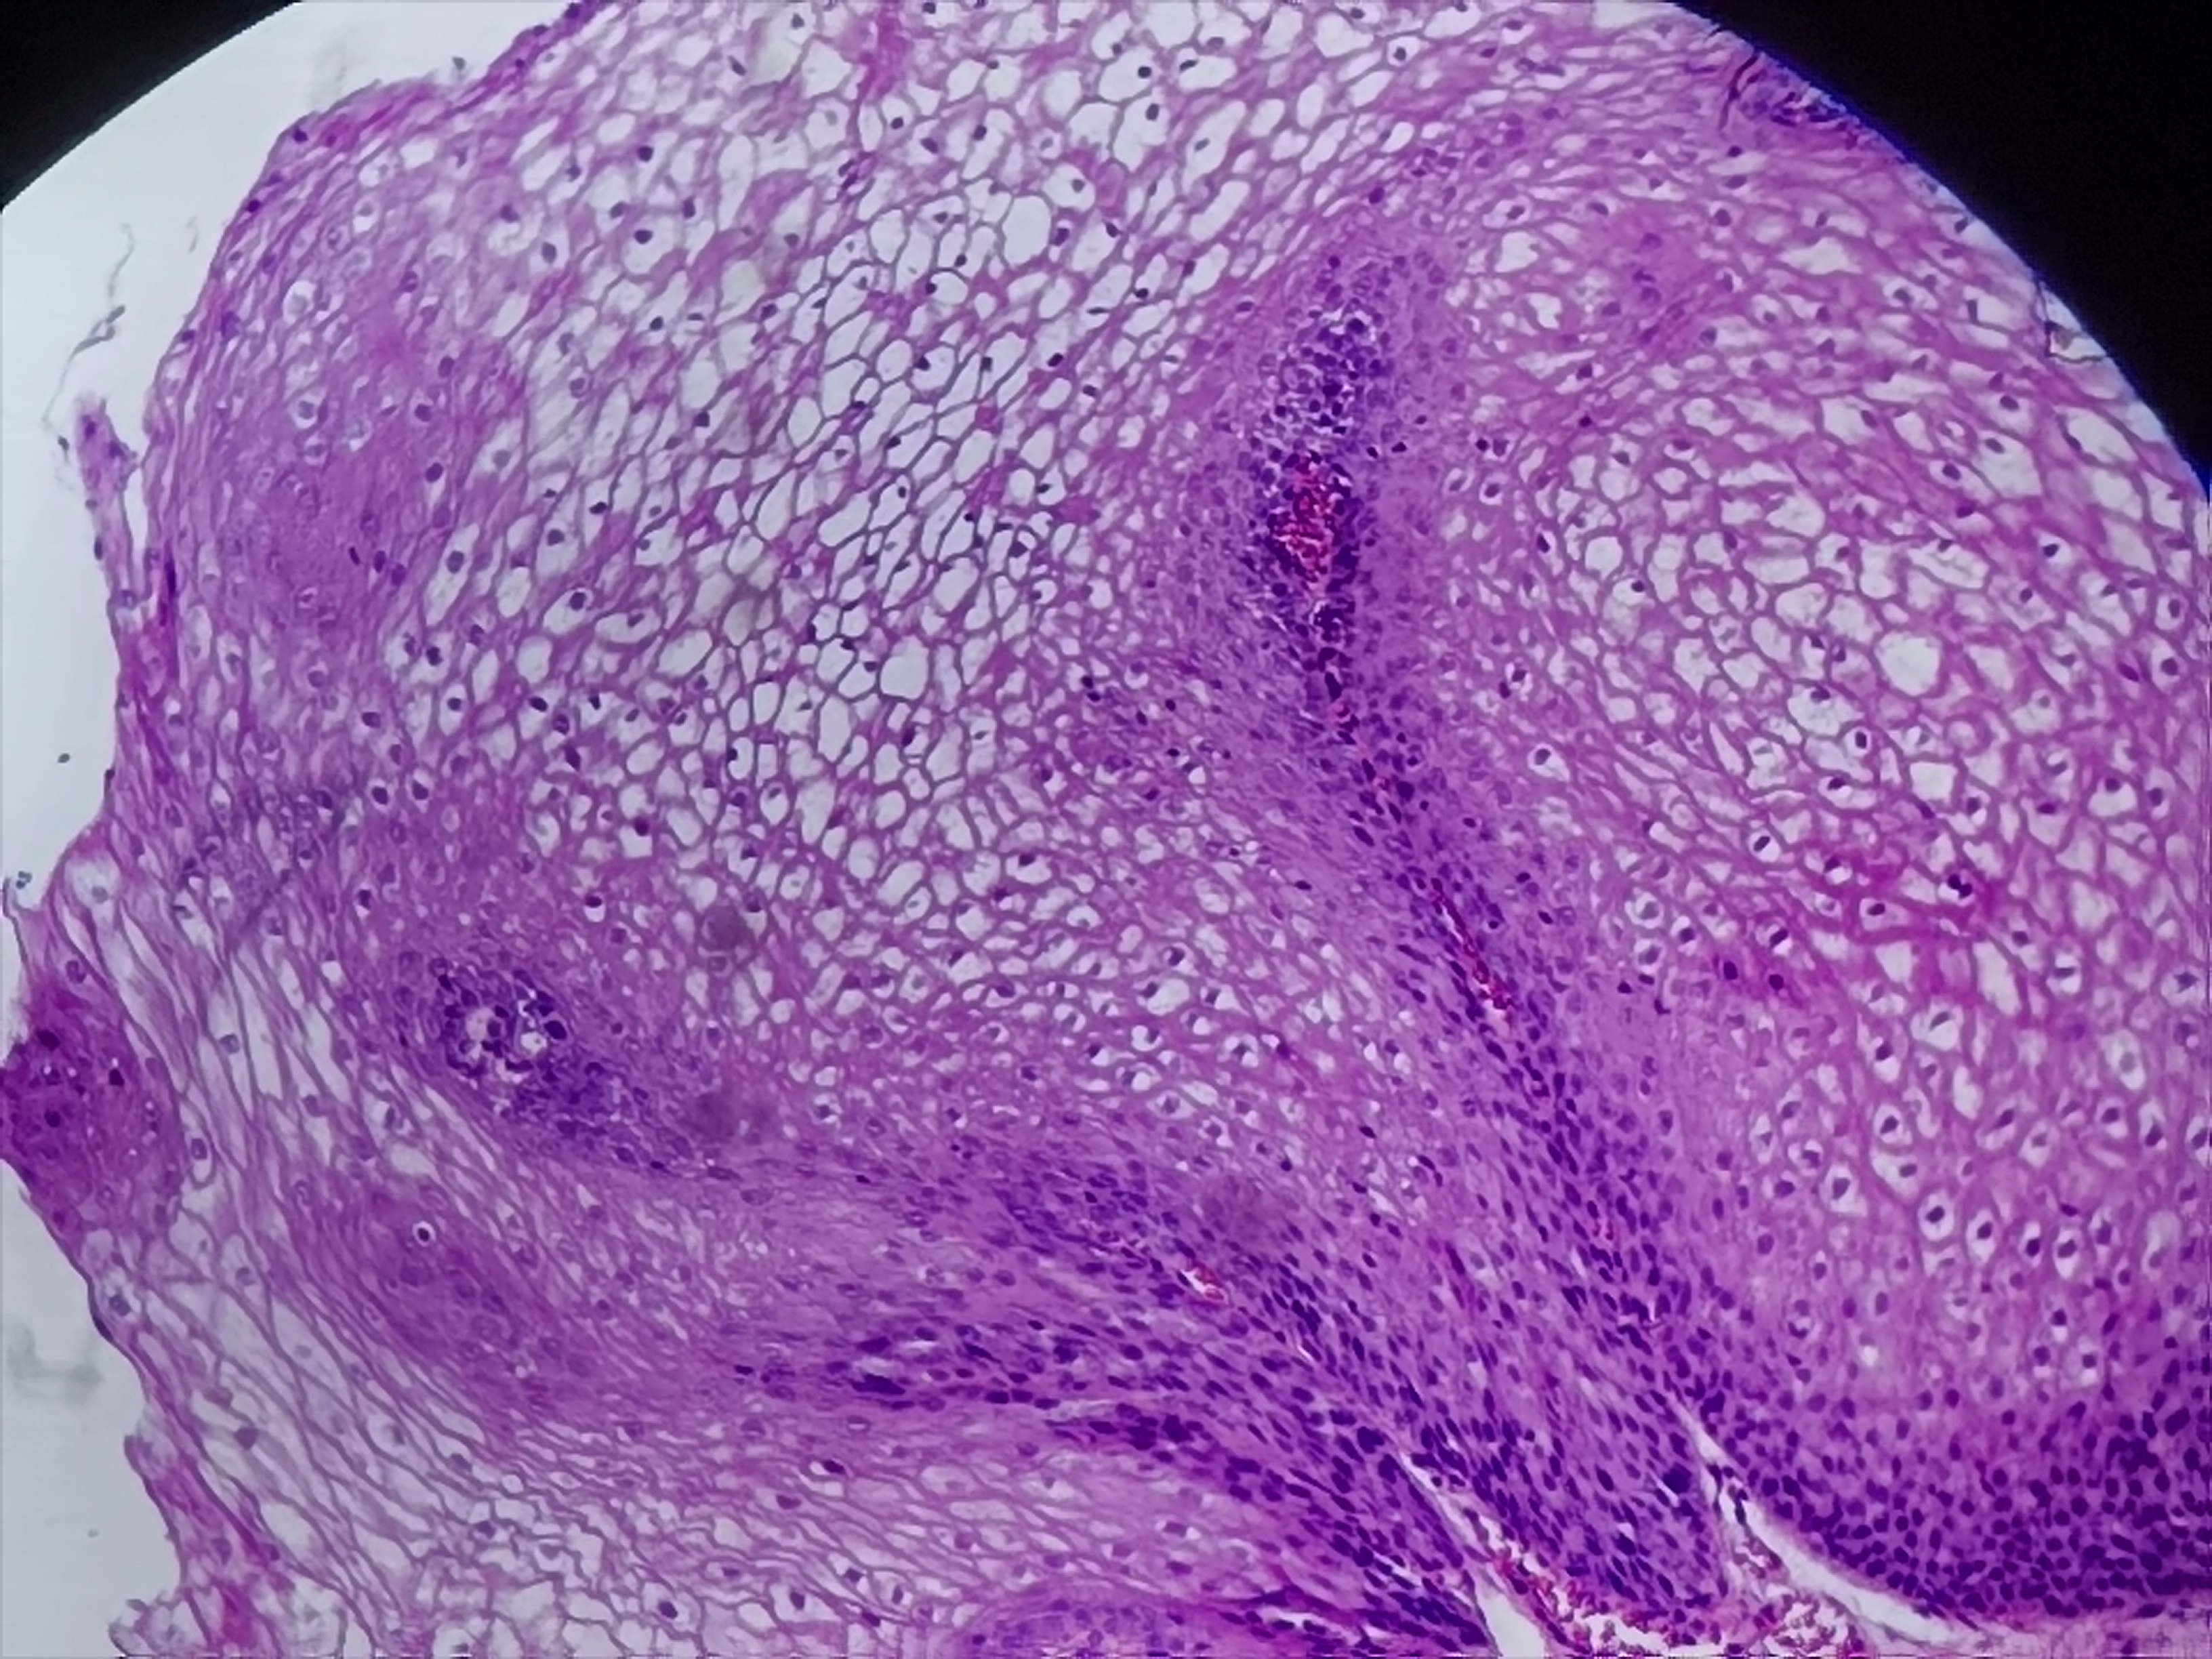

贲门活检

性别

男

年龄

20岁

临床诊断

一般病史

贲门可见糜烂

标本名称

贲门粘膜活检

大体所见

灰白色组织1块

粘膜慢性炎,鳞状上皮增生,固有层淋巴细胞聚集